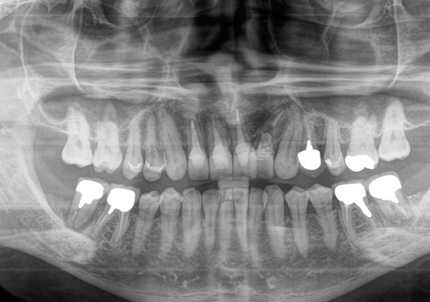

受傷時パノラマレントゲン(2018年5月17日)

初診日 : 2018年5月17日

主訴 :事故により怪我をしたので外科手術の手術回数を少なくしてほしい。今回の治療を最後にして長期予後が良好、安定的な術式を希望する。

治療計画 :

・右上3.1番 歯牙破折… インプラントブリッジ

・左上2番 歯牙破折…インプラントブリッジ

・左上1番 脱落…インプラントブリッジ

・右下1番 脱落…ブリッジ

検討事項:折れた前歯について通常通りの抜歯を行うと顎の骨が溶ける(束状骨の吸収により抜歯窩の形態を維持できず唇・頬側の骨吸収が起こる)。その際に溶けた骨により隣在歯の歯肉と被せ物(補綴物)との連続性が出来ずに凹面になり食べ物(食物残渣)が溜まる状態になる。このストレスを劇的に軽減を可能とするSSTテクニックが近年欧米で発表された。